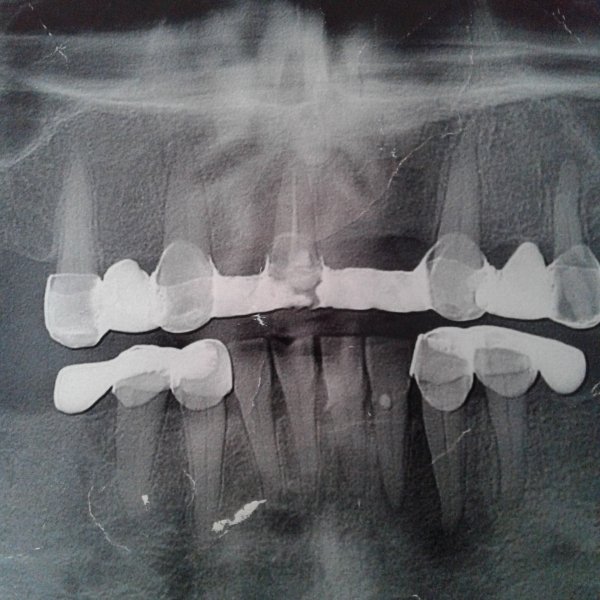

Добрый день. Хотелось узнать про передний зуб. Удаляли нерв года 3 назад, но практически все время реагирует на горячее и холодное и тд. А в апреле сильно опухла десна. Сейчас была у стоматолога сделали снимок сказали, что киста. Подскажите хирургическим ли методом ее надо удалять. Заранее спасибо.

Добрый день, уважаемая Наталья! Судя по снимку, мы имеем очень большую резекцию костной ткани вокруг этого зуба. Эндодонтическим методом такого рода кисту уже вряд ли можно вылечить. Да и резекция судя по снимку не спасет зуб. Я имею ввиду то, что кости и так мало и после резекции, а она подразумевает отсечение инфицированного корня, в кости останется 2-3 мм корня, что недопустимо и достаточной фиксации зуба в кости не будет. Возможно на снимке наложение и мы ошибаемся, поэтому настоятельно рекомендую приехать ко мне на осмотр для принятия решения. Всего вам доброго!